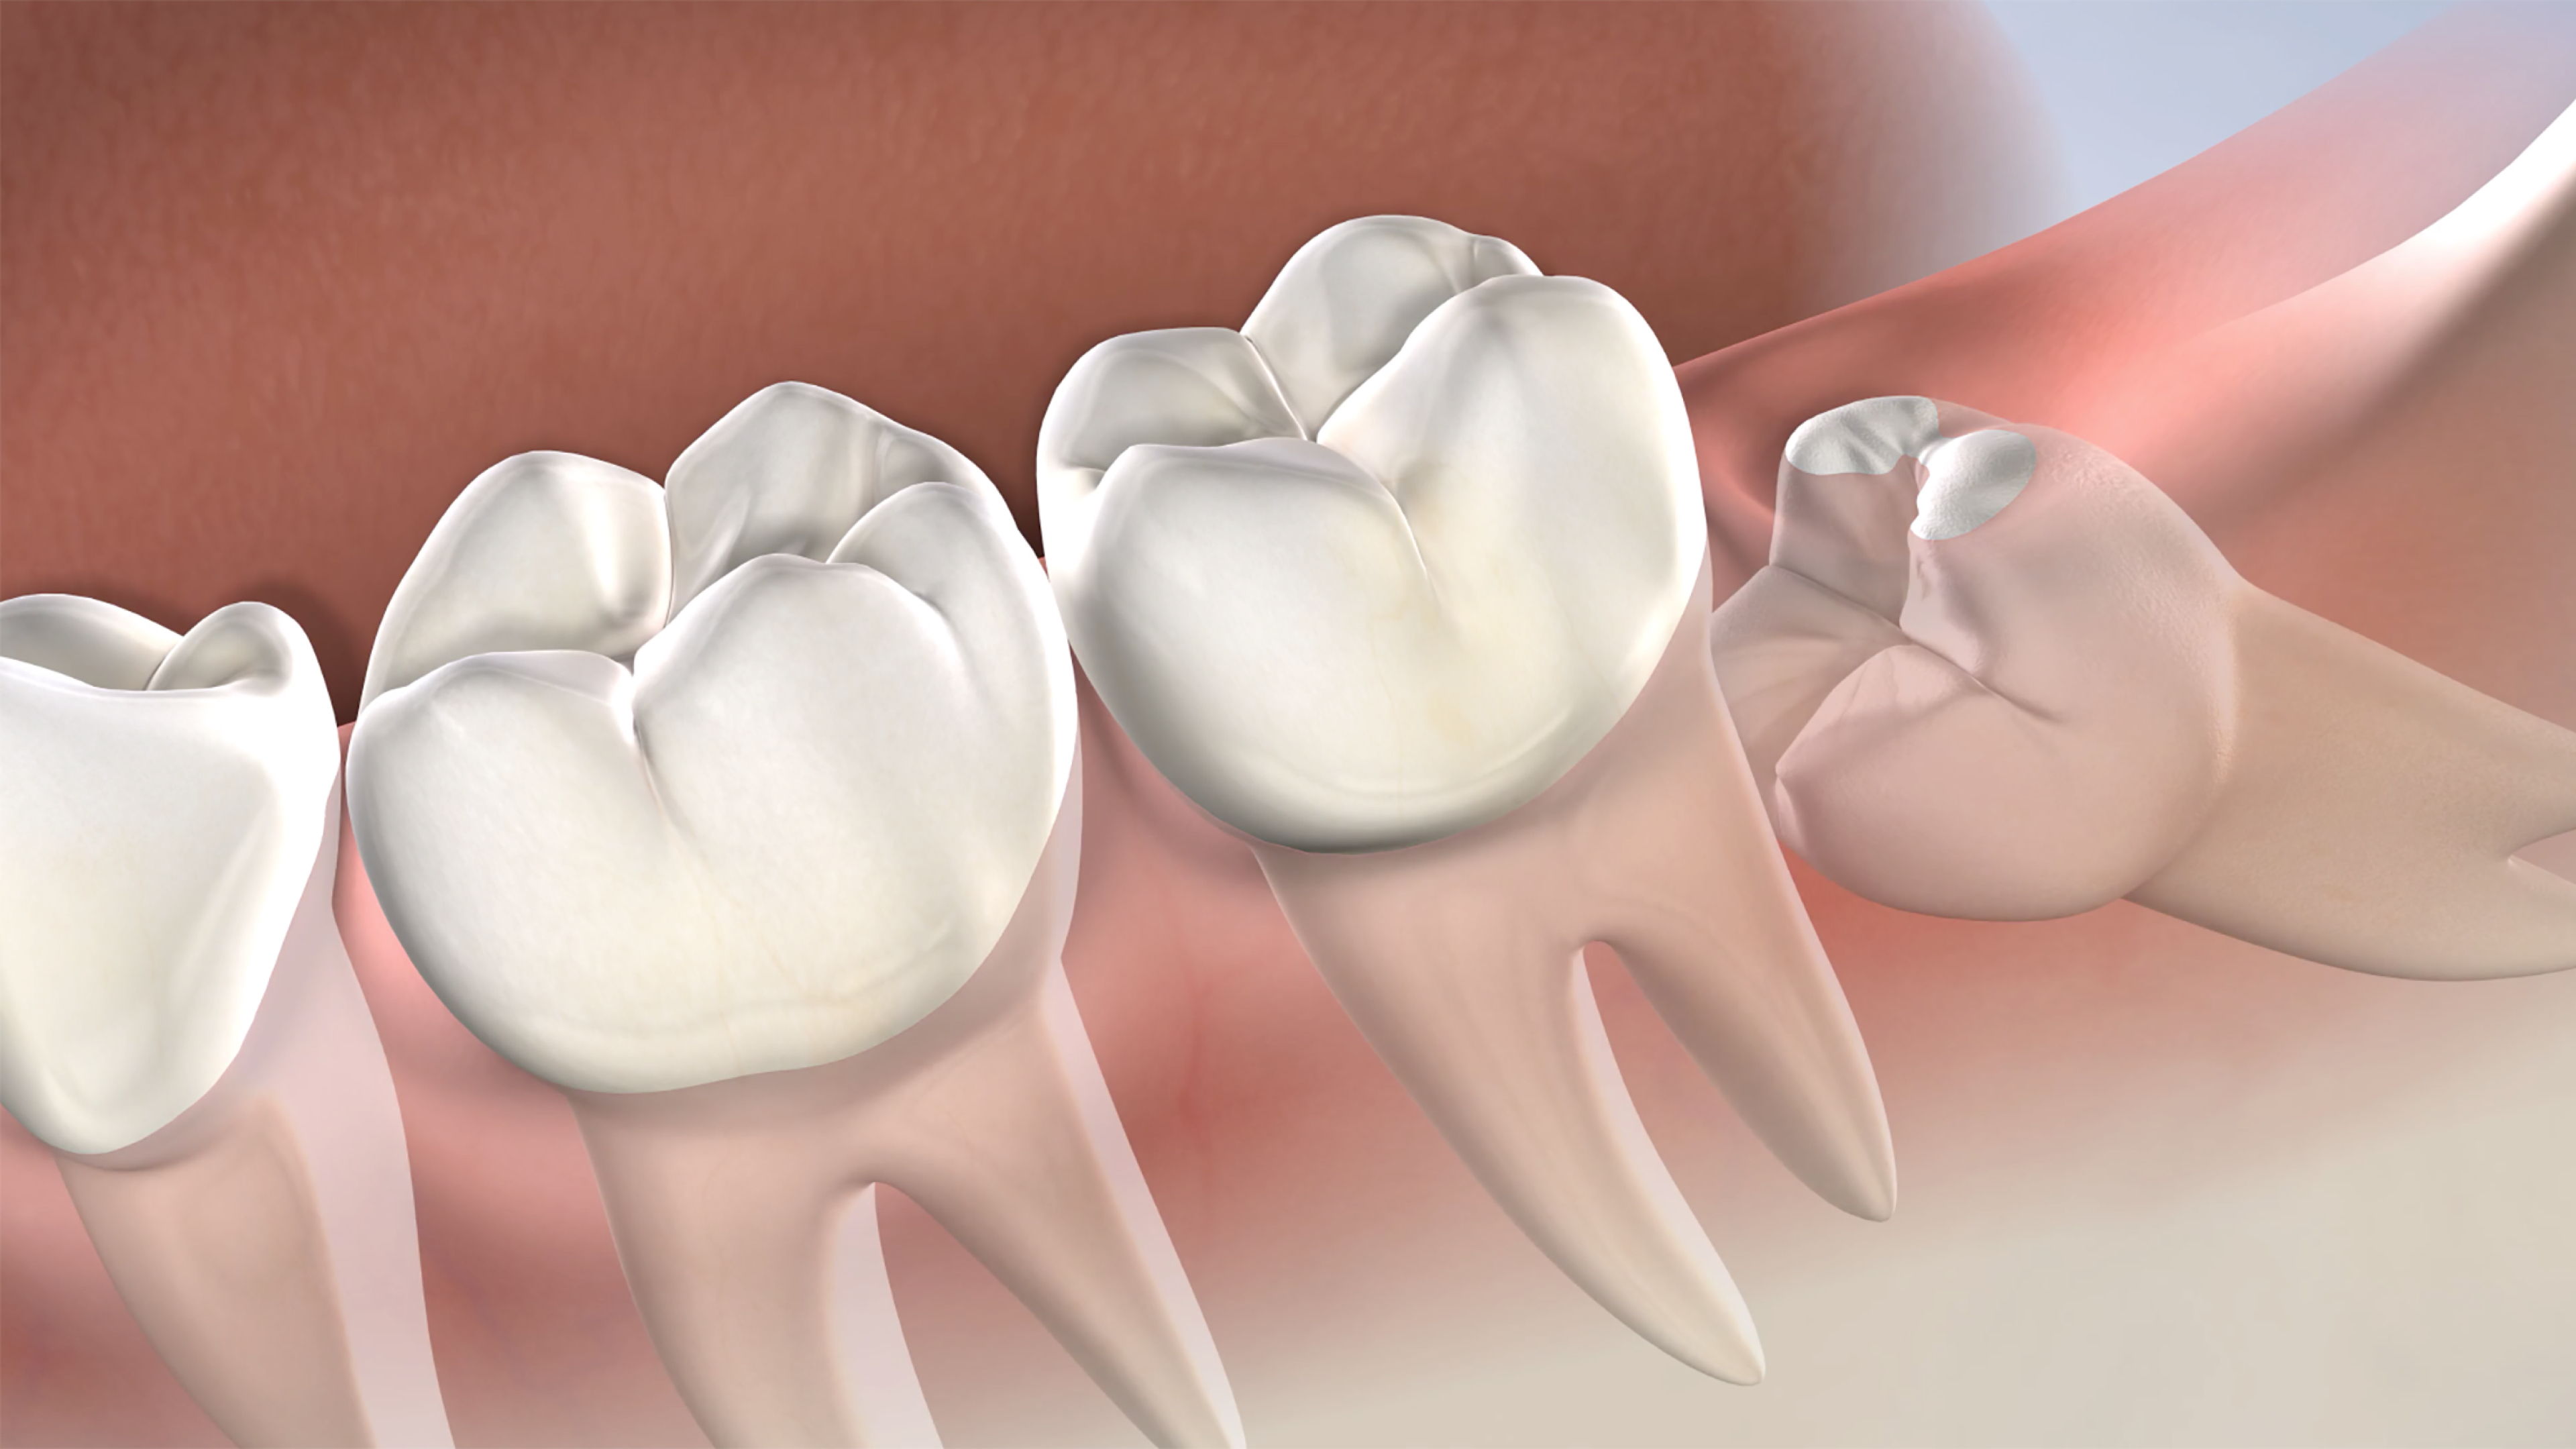

حشو و تركيبات